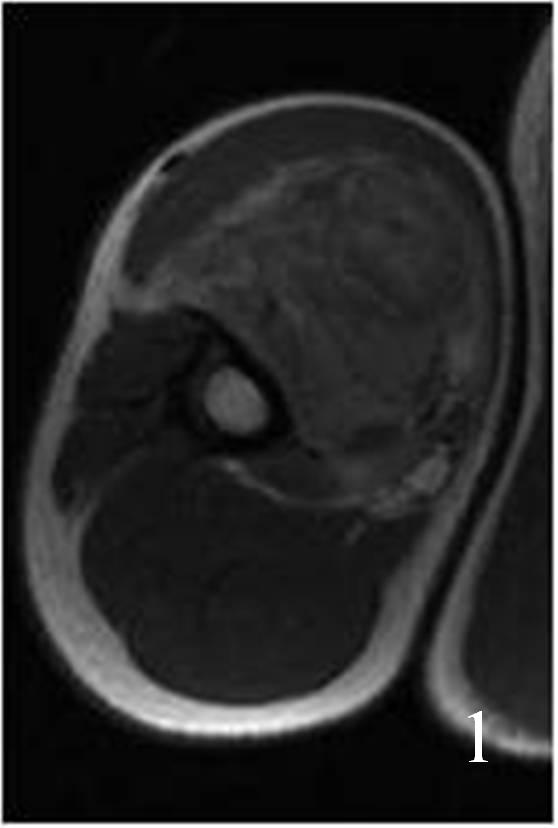

• Intermediate signal isointense to skeletal muscle on T1W (Fig. 1-4)

Fig. 1

Fig. 1-2: Axial (Fig. 1) and coronal (Fig. 2) MRI T1W of an angiosarcoma of the arm shows a well circumscribed heterogeneous lesion. Note the high signal in the center of the mass due to hemorrhage.